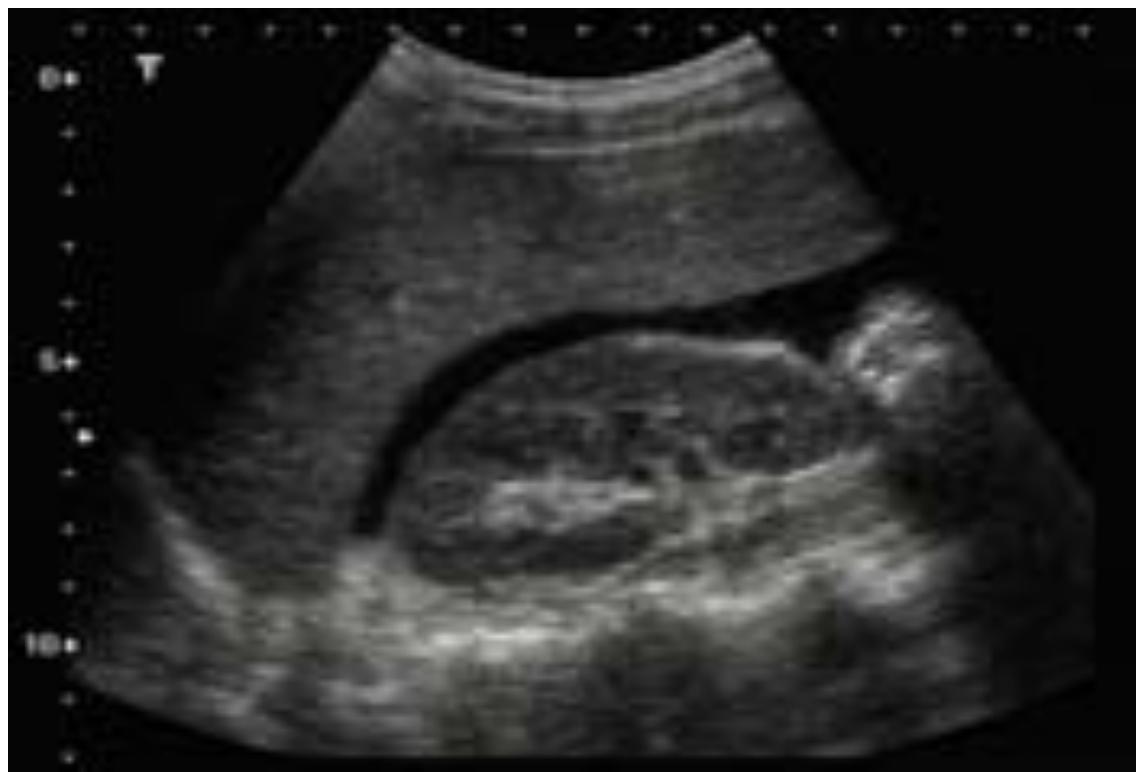

Molar Pregnancy (Complete Mole)

- Diagnosis: Complete Molar Pregnancy.

- Ultrasound Finding: Snowstorm appearance.

- Clinical Presentation:

- Vaginal bleeding in early pregnancy.

- Excessive vomiting (Hyperemesis Gravidarum).

- Hypertension/Preeclampsia before 20 weeks.

- Fundal height greater than gestational age.

- Differential Diagnosis for Early Bleeding: Molar pregnancy, Ectopic pregnancy, Abortion.